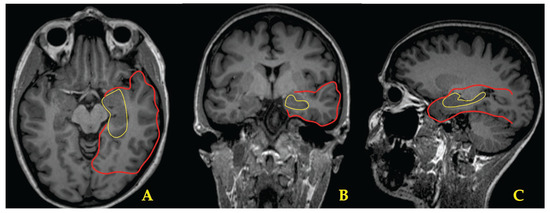

Post-Varicella Arteriopathy as a Cause of Pediatric Arterial Ischemic Stroke: A Systematic Review and Case Report

Background/Objectives: Post-varicella arteriopathy (PVA) is a significant cause of pediatric arterial ischemic stroke (AIS) that typically involves previously healthy children within 12 months of primary varicella infection, mostly with a monophasic course. Diagnosis is based on clinical and imaging findings, and cerebrospinal fluid analysis may confirm it; treatment is empirical and heterogeneous. We describe a typical case of PVA and present a systematic review of its clinical, radiological, therapeutic, and outcome features. Methods: Following PRISMA 2020 and AMSTAR-2 guidelines, data on demographics, clinical presentation, imaging, laboratory confirmation, treatment, and outcomes were extracted across databases (PubMed, Embase, Scopus). Results: Forty-seven studies, encompassing 312 pediatric patients, were included. Mean age was 4 years with a median latency of 3.82 months from varicella to neurologic symptoms. Common presentation included hemiparesis, language impairment, and seizures. Imaging findings showed unilateral focal involvement of anterior circulation arteries, basal ganglia infarctions, and, rarely, bilateral or posterior circulation involvement. CSF VZV-DNA PCR and anti-VZV IgG were positive in 39% and 48% of tested patients. Treatment included intravenous acyclovir (34%), corticosteroids (20%), and low-dose aspirin (77%); two patients underwent acute reperfusion therapy (rt-PA or thrombectomy). Outcomes tended to be moderately favorable: 43% achieved full recovery, 45% had residual deficit, and 11% experienced recurrence. Prothrombotic state was reported, and it may influence disease severity. Conclusions: PVA is a rare distinct cause of pediatric stroke, with a generally favorable prognosis quoad vitam. Standardized guidelines and prospective studies are needed to establish evidence-based management. Clinicians should maintain a high suspicion for its diagnosis. Full article

Show Figures

Figure 1